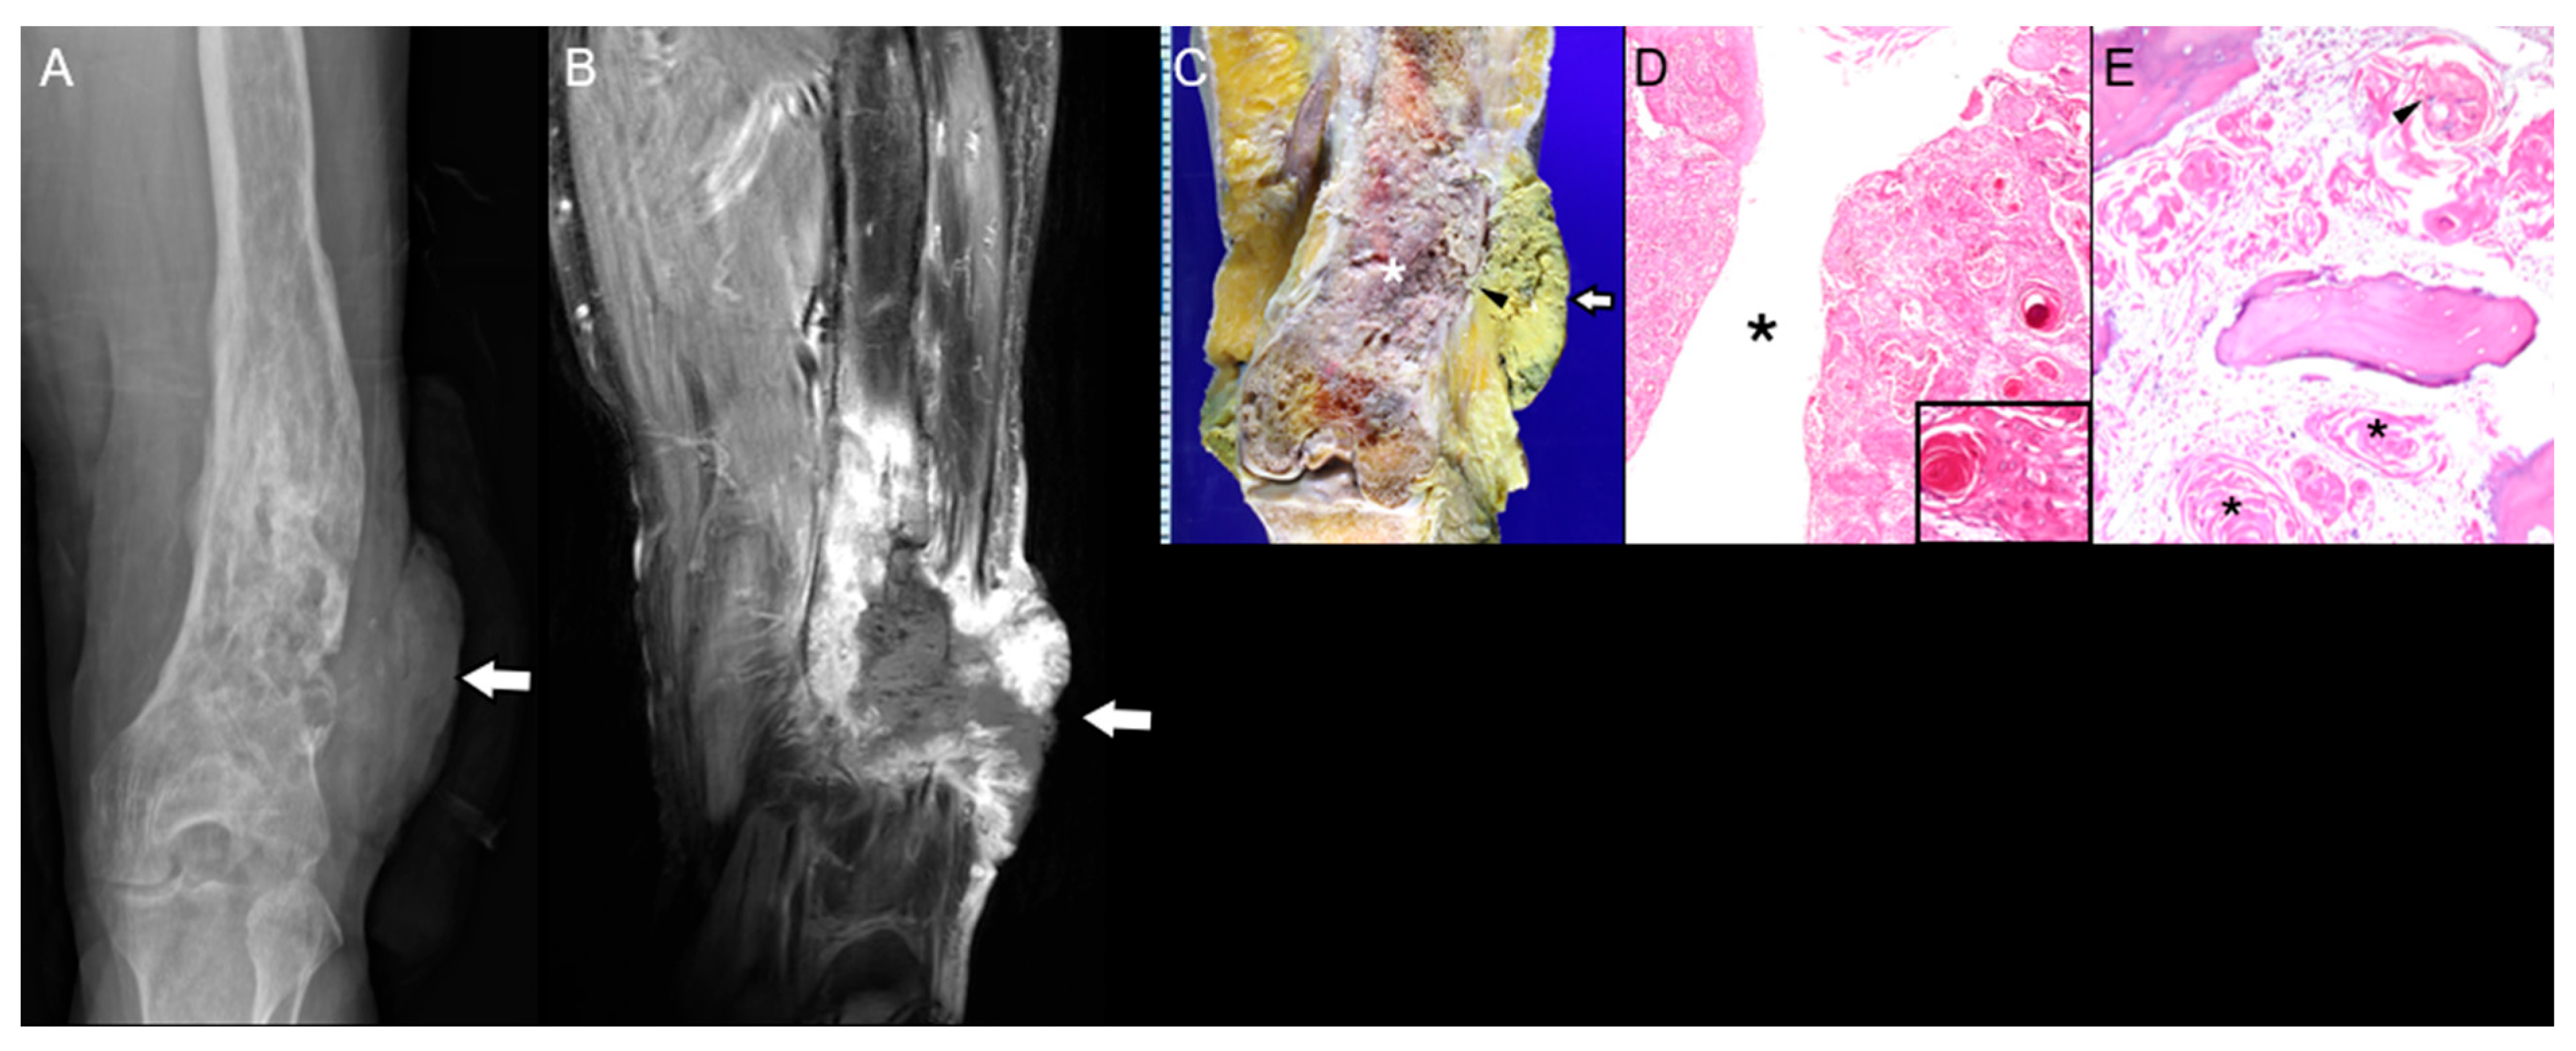

3.2. Bone That Underwent Radiation Therapy